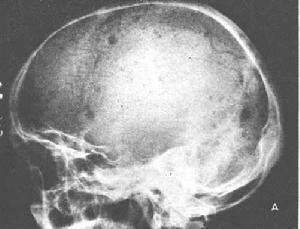

骨髓瘤是中年和晚年(40~60歲)發生的多發惡性骨髓內腫瘤。椎體、肋骨、胸骨、顱骨和骨盆為其好發部位。晚期,股骨和肱骨亦可被累,但膝和肘以下的骨質極少發生。其主要症狀為疼痛,初期為間歇性,繼為持續性,疼痛十分劇烈。神經可能被壓迫,造成放射性疼痛或截癱。腫瘤一旦發現後,多數患者逐漸發生進行性貧血和惡病質變化。但很少產生轉移瘤,肺部極少被累。實驗室檢查可發現以下數種變化:①約50%病例的血清球蛋白增高;②約50%病例的血清鈣增高,有高至18毫克%者;此種病例的甲狀旁腺有繼發性增生;⑧進行性貧血,系因造血機構被腫瘤破壞所致;④少數晚期病例的周圍血液中可能發生假性漿細胞白血病現象,⑤75%病例屎中有凝溶蛋白,⑥約有70%病例在晚期發生腎病。x線檢查時,在被累的骨質中,可以發現多數溶骨性穿鑿形缺損,周圍無反應性新骨增生,此為骨髓瘤的特點。所以病理性骨折較多。椎體發病時,則產生壓縮骨折。四肢發生病理性骨折時,可以引起小量骨膜反應性新骨增生。在顱頂骨中骨髓瘤的典型x線徵象為分布不規則的多發穿鑿形缺損,一見即可識別。但長骨骨幹發病時,骨質的破壞有時與此不同,根據x線照片無法與溶骨性骨肉瘤或轉移瘤區別。

骨髓瘤是中年和晚年(40~60歲)發生的多發惡性骨髓內腫瘤。椎體、肋骨、胸骨、顱骨和骨盆為其好發部位。晚期,股骨和肱骨亦可被累,但膝和肘以下的骨質極少發生。其主要症狀為疼痛,初期為間歇性,繼為持續性,疼痛十分劇烈。神經可能被壓迫,造成放射性疼痛或截癱。腫瘤一旦發現後,多數患者逐漸發生進行性貧血和惡病質變化。但很少產生轉移瘤,肺部極少被累。實驗室檢查可發現以下數種變化:①約50%病例的血清球蛋白增高;②約50%病例的血清鈣增高,有高至18毫克%者;此種病例的甲狀旁腺有繼發性增生;⑧進行性貧血,系因造血機構被腫瘤破壞所致;④少數晚期病例的周圍血液中可能發生假性漿細胞白血病現象,⑤75%病例屎中有凝溶蛋白,⑥約有70%病例在晚期發生腎病。x線檢查時,在被累的骨質中,可以發現多數溶骨性穿鑿形缺損,周圍無反應性新骨增生,此為骨髓瘤的特點。所以病理性骨折較多。椎體發病時,則產生壓縮骨折。四肢發生病理性骨折時,可以引起小量骨膜反應性新骨增生。在顱頂骨中骨髓瘤的典型x線徵象為分布不規則的多發穿鑿形缺損,一見即可識別。但長骨骨幹發病時,骨質的破壞有時與此不同,根據x線照片無法與溶骨性骨肉瘤或轉移瘤區別。[治療]化學治療對多發性骨髓瘤具有一定療效,對有嚴重貧血者可輸血,有截癱者施行椎板切除術,有病理骨折者施用適當的外固定。單發於肢體者,可以考慮截肢。疼痛嚴重者可施行放射線治療。